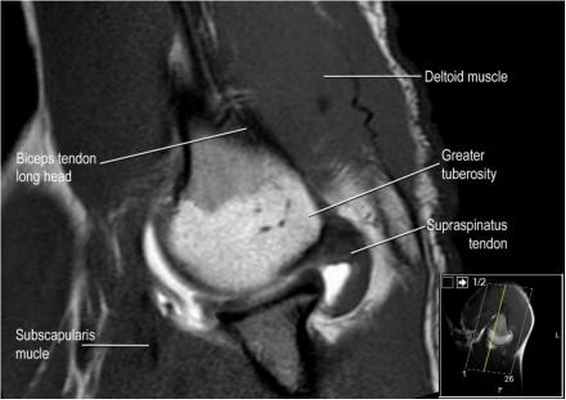

Ось сухожилия надостной мышцы

Подвергаясь тендинопатие и повреждению, сухожилие надостной мышцы является важнейшей частью манжеты вращателей. Повреждения сухожилия надостной мышцы лучше видны в косой корональной плоскости и в положении отведения и поворота плеча кнаружи (ABER - abduction external rotation). В большинстве случаев ось сухожилия надостной мышцы (головки стрелок) отклонена кпереди от оси мышцы (желтая стрелка). При планировании косой корональной проекции лучше ориентироватьия на ось сухожилия надостной мышцы.